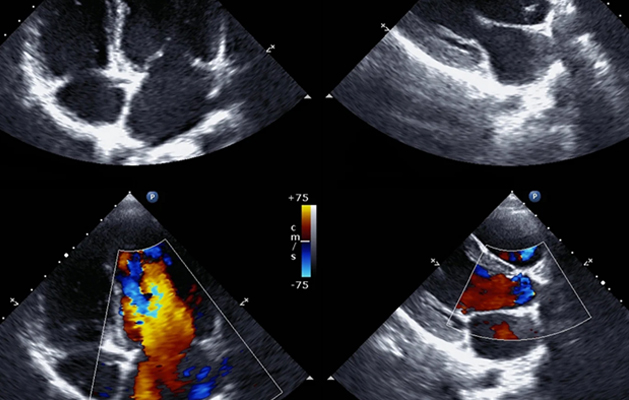

Best Clinical Echocardiogram in Chennai

An echocardiogram is a non-invasive ultrasound test that evaluates heart function. During an echo test, high-frequency sound waves from a hand-held wand placed on your chest provide pictures of the heart’s valves and chamber. These echoes are turned into moving pictures of your heart that can be seen on a video screen to evaluate the pumping action of your heart.

A cardiac echo is used to identify abnormalities in the heart's structure and function. A handheld device sends out sound waves that bounce off your heart and create a moving image of it on a screen. This allows your healthcare provider to look at the anatomy of your heart from many different angles and to observe your heart rhythm.